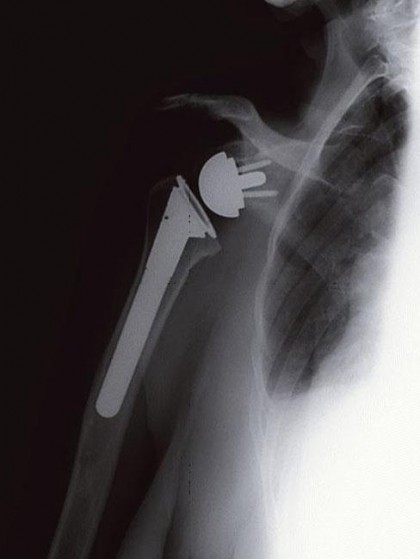

shoulder reversalWe had her first post-op appointment yesterday and got to see an x-ray of the new appliance. This isn’t hers, but it’s an accurate representation of what we saw.  As this image shows, the ball of the shoulder is now where the socket used to be and the socket where the ball used to be. This reverse total shoulder uses different muscles to power the arm, the deltoid in the main. It also reduces pain more for certain patients though I’m not sure why.

Seeing the screws, poking out from the ball, seemed strange to me, but it underscores orthopedics as the carpentry of medicine. Sawbones. The multiple uses of the inclined plane. Thanks, Archimedes.